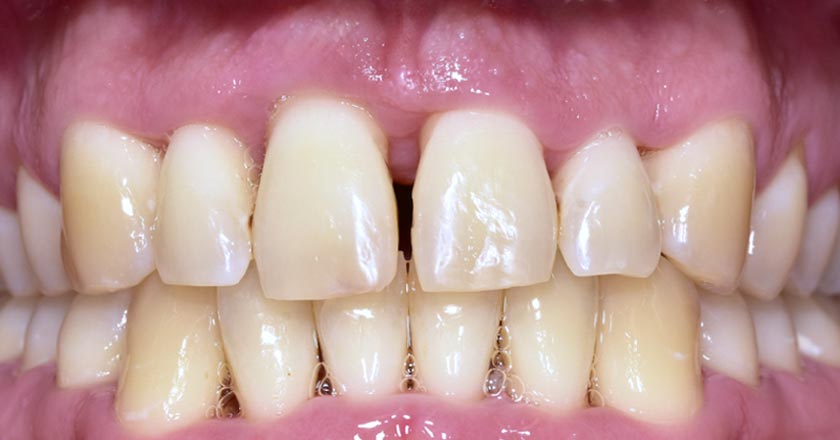

Gummy Smile - Before And After

Gummy smile correction – before treatment 1

Gummy smile correction – after treatment 1